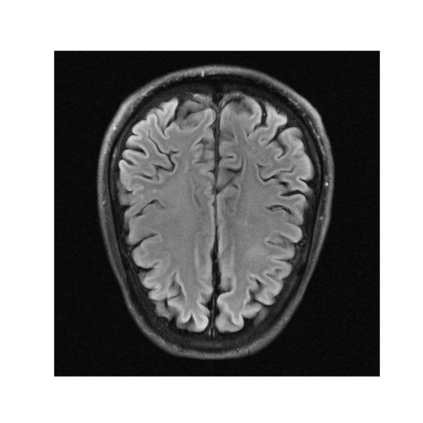

In spite of its extensive adaptation in almost every medical diagnostic and examinatorial application, Magnetic Resonance Imaging (MRI) is still a slow imaging modality which limits its use for dynamic imaging. In recent years, Parallel Imaging (PI) and Compressed Sensing (CS) have been utilised to accelerate the MRI acquisition. In clinical settings, subsampling the k-space measurements during scanning time using Cartesian trajectories, such as rectilinear sampling, is currently the most conventional CS approach applied which, however, is prone to producing aliased reconstructions. With the advent of the involvement of Deep Learning (DL) in accelerating the MRI, reconstructing faithful images from subsampled data became increasingly promising. Retrospectively applying a subsampling mask onto the k-space data is a way of simulating the accelerated acquisition of k-space data in real clinical setting. In this paper we compare and provide a review for the effect of applying either rectilinear or radial retrospective subsampling on the quality of the reconstructions outputted by trained deep neural networks. With the same choice of hyper-parameters, we train and evaluate two distinct Recurrent Inference Machines (RIMs), one for each type of subsampling. The qualitative and quantitative results of our experiments indicate that the model trained on data with radial subsampling attains higher performance and learns to estimate reconstructions with higher fidelity paving the way for other DL approaches to involve radial subsampling.